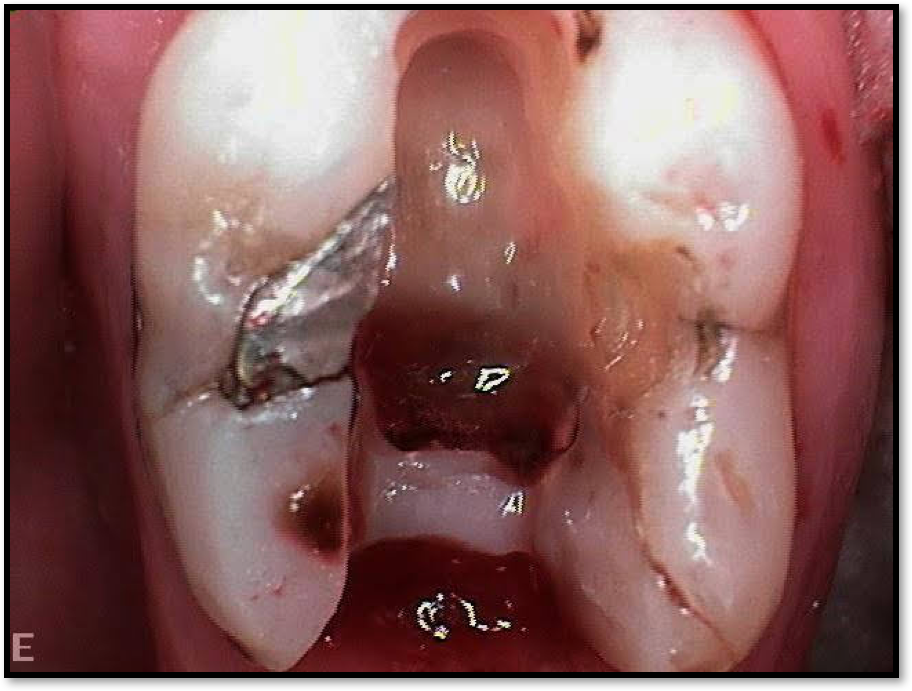

Figure 2 shows a situation where the clinician excavated the tooth of a patient with decay, and it pulped out. The buccal and lingual walls were intact; however, the walls were minimal, and there were still fragments of amalgam and cracks. If the clinician prepared this tooth after building it up, the clinician would lose all the good tooth structure that was left. This tooth would likely need a post.

Fig 2. Minimal walls.

Figure 2